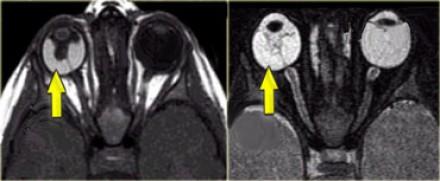

Атерома мрт

Атерома мрт 113 фото